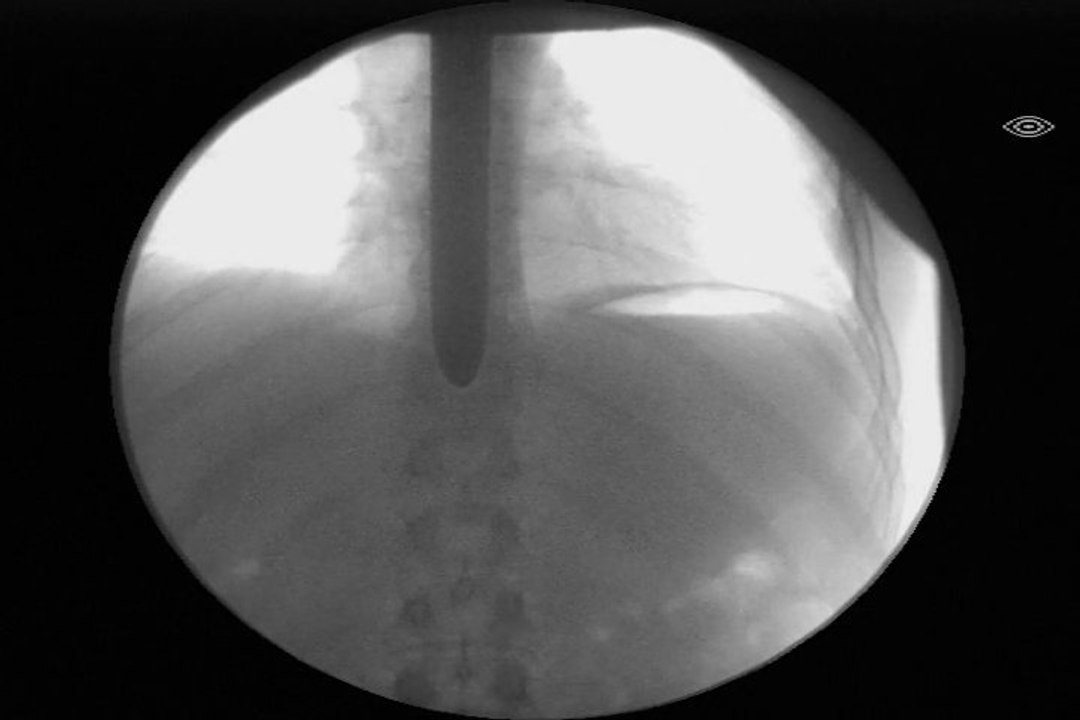

Sword Swallower Dan Meyer swallows 10 swords and Hedge Clippers in 4 minutes with Cirque Eloize for "La Vie est un Cirque" in Montreal! Watch as TV Film star Patrice Bélanger whips a sword out of Dan's mouth! Used by permission. <br /> <br />Sword Swallower Dan Meyer is a 40x World Champion Sword Swallower, multiple Ripley's Believe It or Not with 7 Guinness World Records and Finalist on America's Got Talent, known as the world's top sword swallower and leading expert in the field as president of the Sword Swallowers Association International, global TED speaker, and winner of the 2007 Ig Nobel Prize in Medicine at Harvard for sword swallowing medical research. <br /> <br />As a performer, Sword Swallower Dan Meyer is best known as the "Most Dangerous Act" that wowed the judges on America's Got Talent to Las Vegas and Hollywood, for his dangerous feats and extreme daredevil stunts such as swallowing swords underwater in a tank of SHARKS for Ripley's Believe It or Not, for swallowing a sword heated to 1500 degrees RED HOT for Stan Lee's Superhumans, swallowing 29 swords AT ONCE, and for PULLING a 3700 lb CAR by swallowed sword for Ripley's Believe It or Not Baltimore and on America's Got Talent Season 11, Italy's Got Talent and France's Got Talent. <br /> <br />http://CuttingEdgeInnertainment.com <br /> <br />Instagram: @Halfdan5 <br />http://instagram.com/Halfdan5 <br />http://www.danmeyer.org <br />http://twitter.com/Halfdan